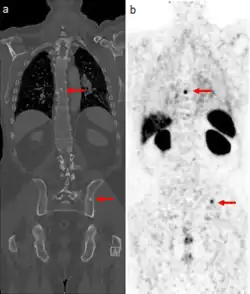

The main (67Ga) technique uses scintigraphy to produce two-dimensional images. After the tracer has been injected, images are typically taken by a gamma camera at 24, 48, and in some cases, 72, and 96 hours later.[21][22] Each set of images takes 30–60 minutes, depending on the size of the area being imaged. The resulting image will have bright areas that collected large amounts of tracer, because inflammation is present or rapid cell division is occurring. Single-photon emission computed tomography (SPECT) images may also be acquired. In some imaging centers, SPECT images may be combined with computed tomography (CT) scan using either fusion software or SPECT/CT hybrid cameras to superimpose both physiological image-information from the gallium scan, and anatomical information from the CT scan.